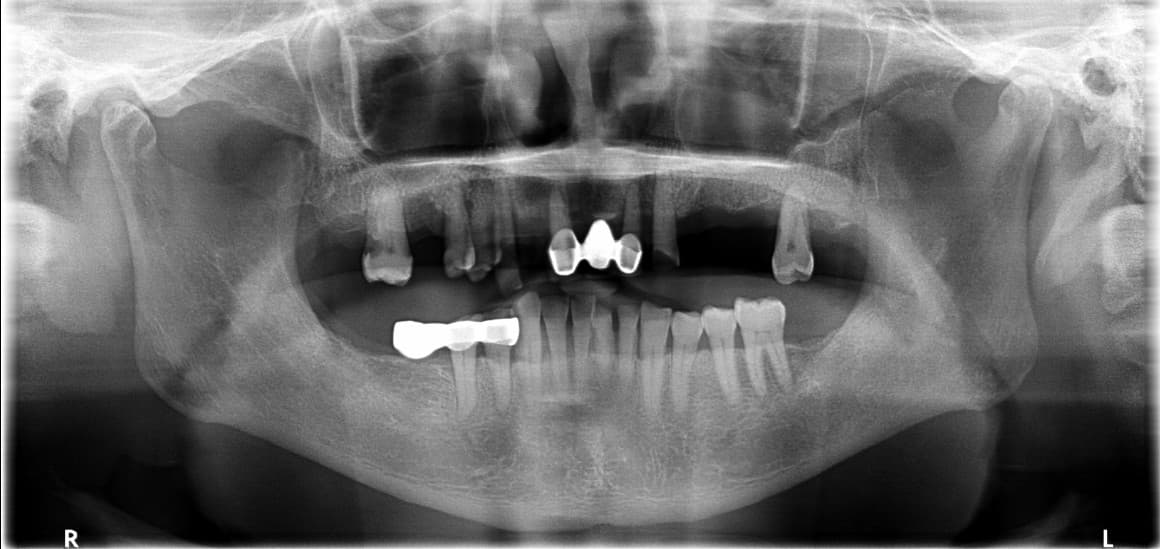

COST-EFFECTIVE TREATMENT

Protez mutaxassisi tomonidan

shaxsiy og'iz bo'shlig'ini tiklash

Implant, toj, ko'prik va boshqalar

Bemor holatiga mos eng maqbul davolash kombinatsiyasi bilan

maqbul narxda eng yaxshi natija

After ✨

Kang●● · 50 yoshdan oshgan erkak

Implant + Toj + Ko'prik kombinatsiyasi

Song●● · 60 yoshdan oshgan ayol

Shaxsiy protez kombinatsiyasi davolash

Jo●● · 50 yoshdan oshgan ayol

Tejamkor shaxsiy davolash